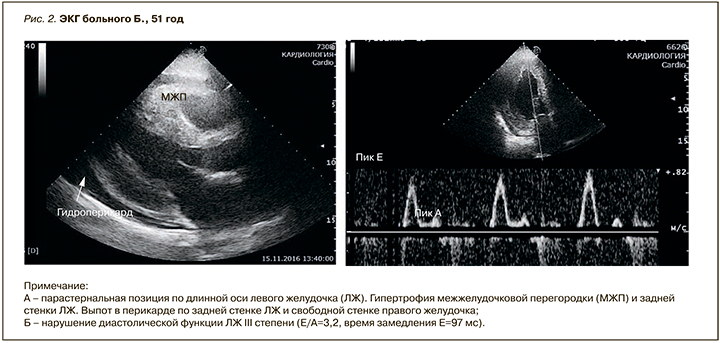

По данным эхокардиографии (ЭхоКГ) выявлена выраженная концентрическая гипертрофия левого желудочка (ЛЖ) с толщиной межжелудочковой перегородки (МЖП) до 1,8 мм и задней стенки до 1,7 мм, индексированная масса миокарда ЛЖ – 164 г/м2. Индекс относительной толщины стенки ЛЖ – 0,65. Конечно-диастолический объем ЛЖ составил 90 мл, конечно-систолический – 64 мл, фракция выброса (ФВ) – 29%. Обнаружены гипокинез всех сегментов ЛЖ, увеличение обоих предсердий. Конечно-систолический объем левого предсердия – 63 мл/ м2, правого – 42 мл/м2. Систолическое давление в легочной артерии – 43 мм рт.ст. Выявлены небольшая недостаточность митрального и трикуспидального клапанов, диастолическая дисфункция ЛЖ III степени (Е/ А=3,2, время замедления Е=97 мс). В полости перикарда умеренное количество выпота (рис. 2).